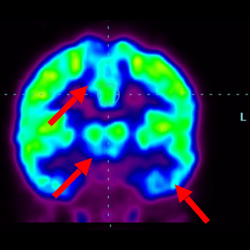

細(xì)胞治療后,藍(lán)色和黑色區(qū)域減少,并且看到更活躍的區(qū)域。這表明損傷減少并改善了大腦功能。

這證明細(xì)胞療法是治療腦癱兒童安全有效的方法。細(xì)胞療法可以更新大腦損傷的核心,并且可以通過 PET CT 掃描來監(jiān)測大腦的改善情況。這些細(xì)胞療法與標(biāo)準(zhǔn)治療一起促進(jìn)腦癱兒童的生長和改善。